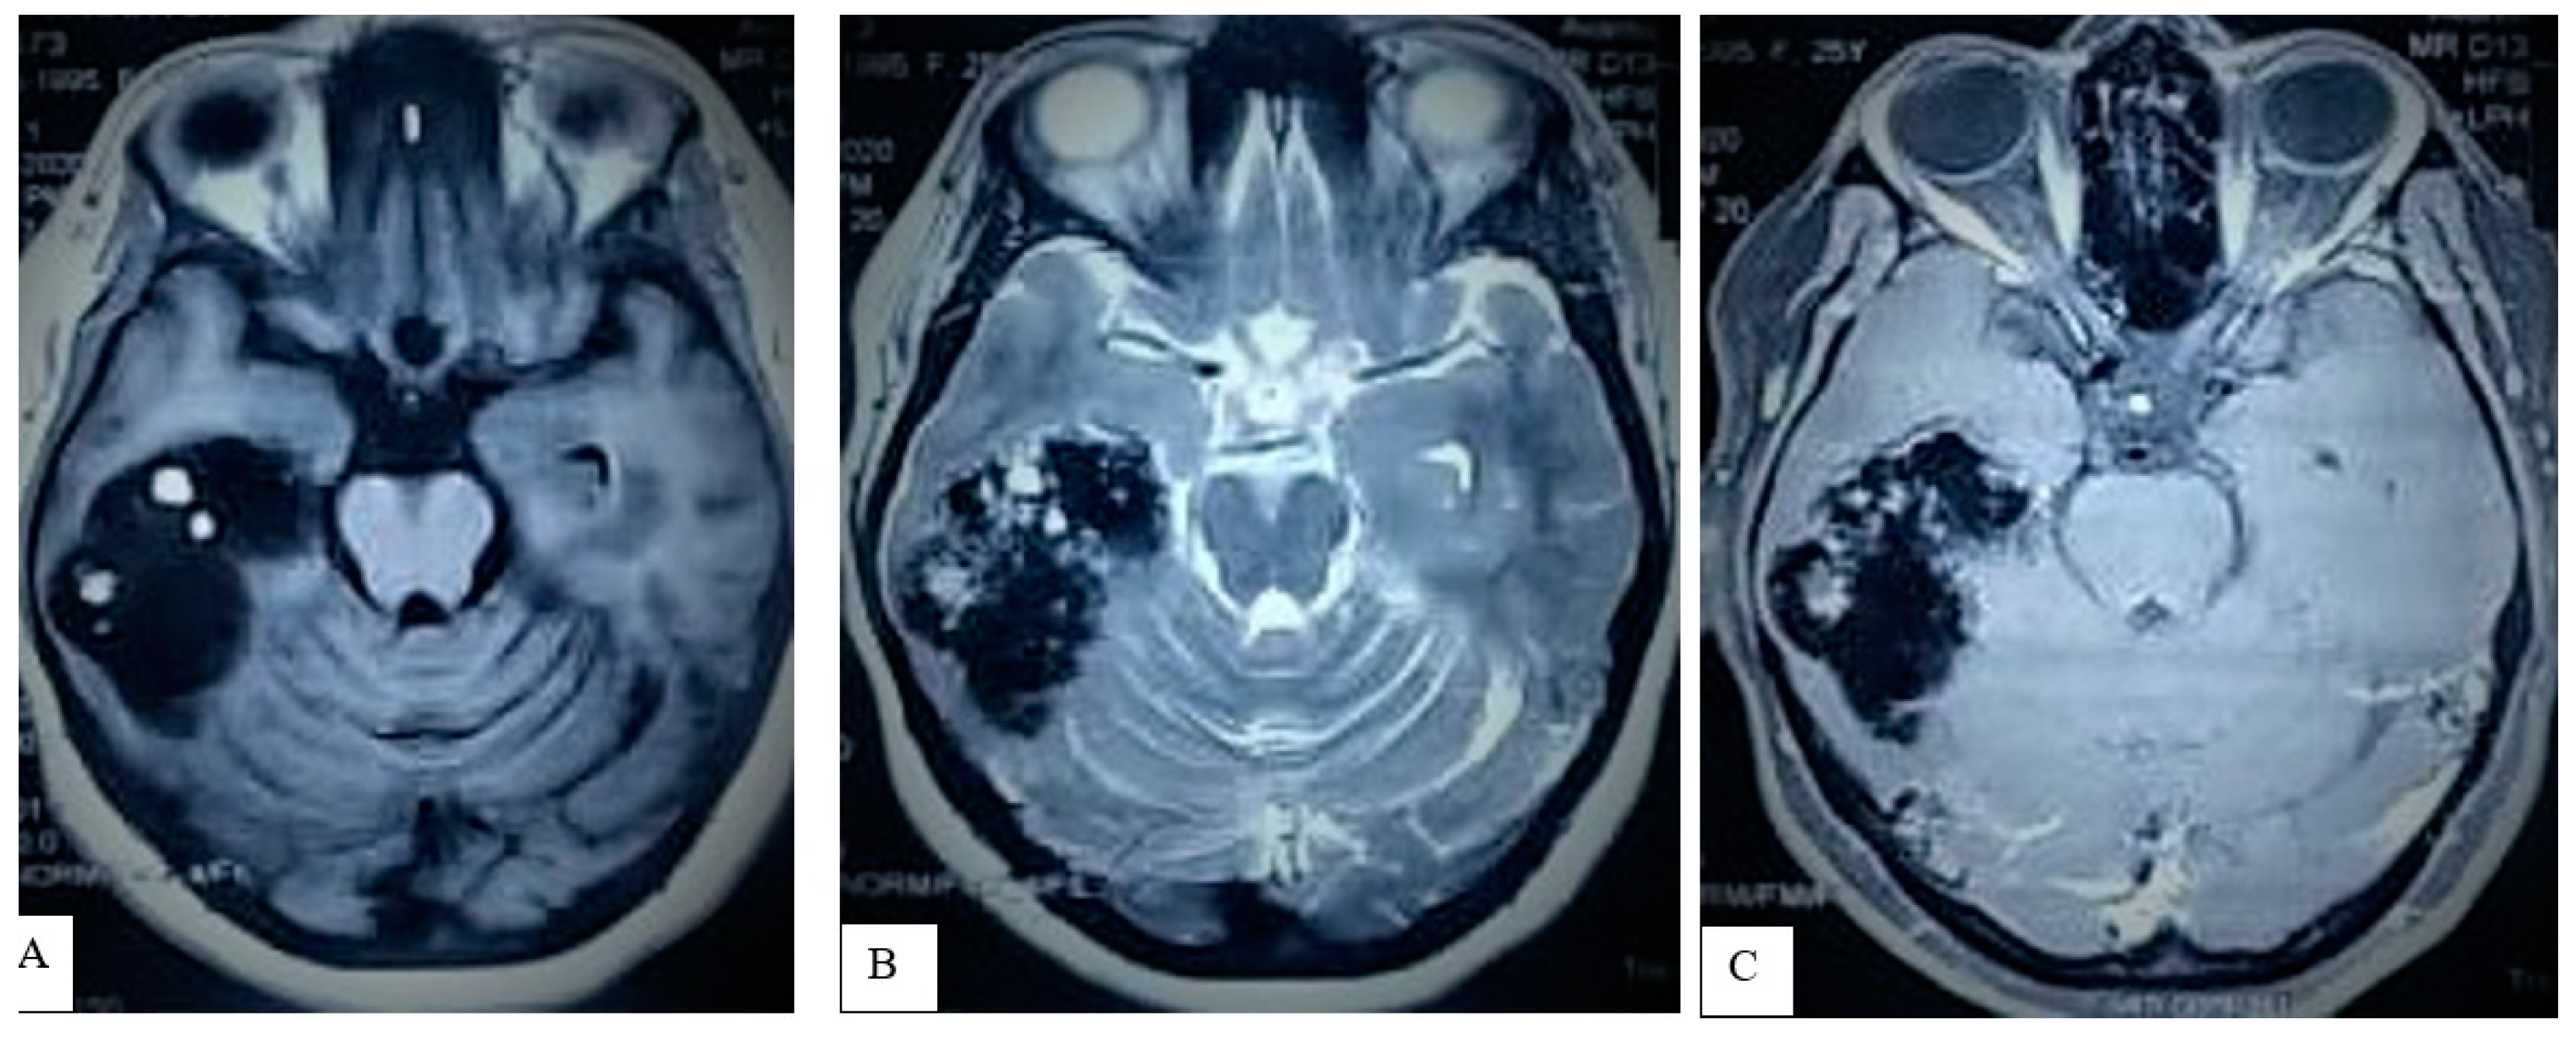

3.1.2. Preoperative Imaging

| 32 | Present case | 2021 | 25 | F | R | Headache, seizure, visual disturbances | Solid calcified mass | GTR | No recurrence at 6 months |